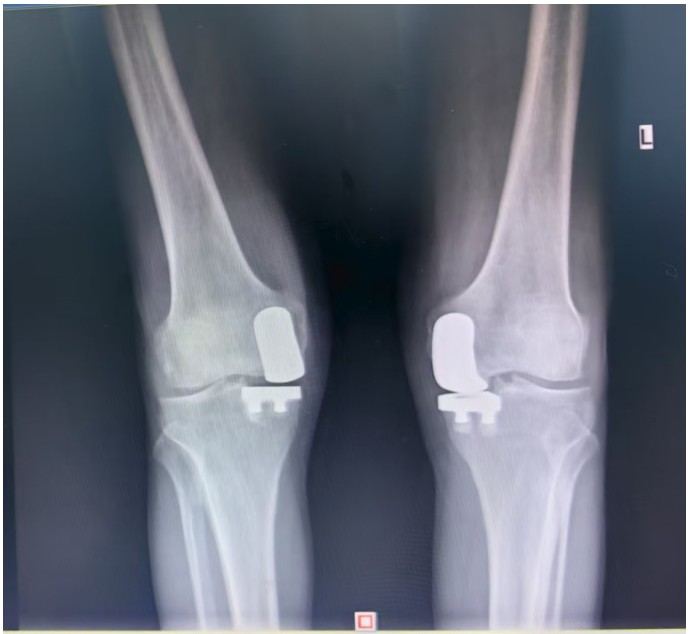

通訊員王珂報(bào)道:近日,一位來(lái)自江西的大爺跨越六百公里,專程來(lái)到衡陽(yáng)市中心醫(yī)院關(guān)節(jié)外科求診。羅湘平主任醫(yī)師、彭健副主任醫(yī)師團(tuán)隊(duì)熱情地接待了患者,并成功為其實(shí)施了“雙側(cè)人工膝關(guān)節(jié)單髁置換術(shù)(UKA)”。術(shù)后膝關(guān)節(jié)功能顯著改善,第二天便可下地活動(dòng),雙側(cè)膝關(guān)節(jié)活動(dòng)度輕松達(dá)到90°,對(duì)手術(shù)效果非常滿意,已于9月10日順利出院。

據(jù)了解,患者1年前無(wú)明顯誘因出現(xiàn)雙膝關(guān)節(jié)疼痛,以右側(cè)膝關(guān)節(jié)為主,近5個(gè)月來(lái)雙膝關(guān)節(jié)疼痛明顯加重,不但日常行走困難,生活質(zhì)量更是受到極大影響。經(jīng)多家醫(yī)院治療效果均不理想,了解到衡陽(yáng)市中心醫(yī)院關(guān)節(jié)外科在關(guān)節(jié)置換領(lǐng)域擁有豐富的臨床經(jīng)驗(yàn)和良好的患者口碑,毅然決定赴衡求醫(yī)。醫(yī)生發(fā)現(xiàn)患者雙膝關(guān)節(jié)已有內(nèi)翻畸形,關(guān)節(jié)內(nèi)側(cè)骨性膨大,X線提示雙膝退行性病變,雙膝內(nèi)側(cè)間隙明顯狹窄,手術(shù)為最佳治療方式。為了達(dá)到根治目的,羅湘平主任醫(yī)師、彭健副主任醫(yī)師為患者進(jìn)行了詳細(xì)查體及綜合評(píng)估,術(shù)前組織開(kāi)展多學(xué)科討論(MDT)。考慮到易叔叔的膝關(guān)節(jié)骨關(guān)節(jié)炎僅局限于內(nèi)側(cè),外側(cè)間室軟骨良好,若采用全膝關(guān)節(jié)置換術(shù)會(huì)將失去正常關(guān)節(jié)間室的軟骨與韌帶,創(chuàng)傷較大,便為其制定了右膝關(guān)節(jié)單髁置換手術(shù)治療方案。在充分完善術(shù)前準(zhǔn)備后,羅湘平主任、彭健副主任醫(yī)師團(tuán)隊(duì)為患者實(shí)施了右側(cè)膝關(guān)節(jié)單髁置換術(shù)。手術(shù)過(guò)程順利,團(tuán)隊(duì)?wèi)?yīng)用微創(chuàng)術(shù)式(MIS)及“精準(zhǔn)間隙平衡技術(shù)”,最大程度減少了手術(shù)創(chuàng)傷,為術(shù)后快速康復(fù)奠定了堅(jiān)實(shí)基礎(chǔ),術(shù)后第二天即可借助助行器下地活動(dòng)。6天后團(tuán)隊(duì)順利為患者實(shí)施了左側(cè)膝關(guān)節(jié)單髁置換手術(shù)。目前,易叔叔在關(guān)節(jié)外科醫(yī)護(hù)團(tuán)隊(duì)的精心指導(dǎo)和康復(fù)治療下,恢復(fù)情況良好,雙側(cè)膝關(guān)節(jié)活動(dòng)度輕松達(dá)到90°,膝關(guān)節(jié)功能顯著改善,能夠獨(dú)立下地行走,對(duì)手術(shù)效果非常滿意,已于9月10日順利出院。

羅湘平主任介紹,膝單髁置換術(shù)是針對(duì)膝關(guān)節(jié)單側(cè)間室病變的微創(chuàng)手術(shù),該術(shù)式通過(guò)置換單側(cè)股骨或脛骨受損軟骨表面,保留交叉韌帶及正常骨質(zhì)結(jié)構(gòu),因創(chuàng)傷小、恢復(fù)快被稱為膝關(guān)節(jié)置換中的“補(bǔ)牙”技術(shù),適用于單間室骨關(guān)節(jié)炎且韌帶功能完整的患者。膝關(guān)節(jié)單髁置換為特定的膝關(guān)節(jié)疾病患者提供了一種較為理想的治療選擇,它以較小的手術(shù)創(chuàng)傷、良好的術(shù)后功能恢復(fù)效果,幫助患者緩解疼痛,恢復(fù)正常的生活和活動(dòng)能力。